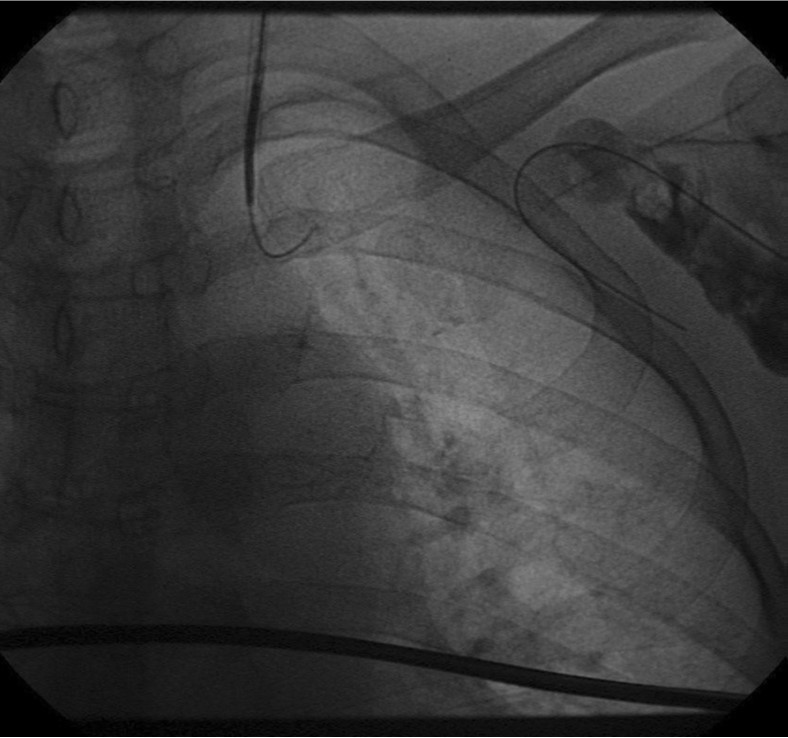

환자의 AV fistula는 초음파상 total thrombotic occlusion 된 상태였으며 시술 전 urokinase 100000 unit를 사용하여 thrombolysis and aspirated thrombectomy를 시행하였다. 그 후 시행한 shuntogram(Fig. 1) 상 left basilic vein 의 total ocdusion을 보이며 초음파상 remant vein의 크기는 1mm 이하로 확인되었다. 투시하에서 확인되는 outflow vein은 없었기에 초음파 유도하에 5 Fr Kumpe catheter(Soft-Vu, AngioDynamics, USA, NY) 에 0.035’ straight-tip guide wire(Terumo, Tokyo, Japan)를 사용하여 막힌 left basilic vein으로 15cm 이상 진행하였으며(Fig. 3), 4mm balloon (synergy, Boston, Ireland)를 사용하여 blind angioplasty를 하며 true lumen으로의 진행을 시도하였으나 실패하였다(Fig. 4). 더 이상의 antegrade로의 접근은 어려울 것으로 판단하여 regrograde approach를 위하여 left internal jugular vein 을 초음파 유도하에 9Fr sheath( Accu-Sheath, Sungwonmedical, Korea, Cheongju)을 사용하여 access 하였다. (Fig. 5A) 그리고 5Fr Cobra & sherpherd hook catheter (A&A M.D., Korea, Sungnam) 를 이용하여 left axillary vein으로의 접근을 시도하였다(Fig. 5B).

Fig. 5.

A-B. Retrograde guide wire negotiation to left basilica vein via transjugular approach